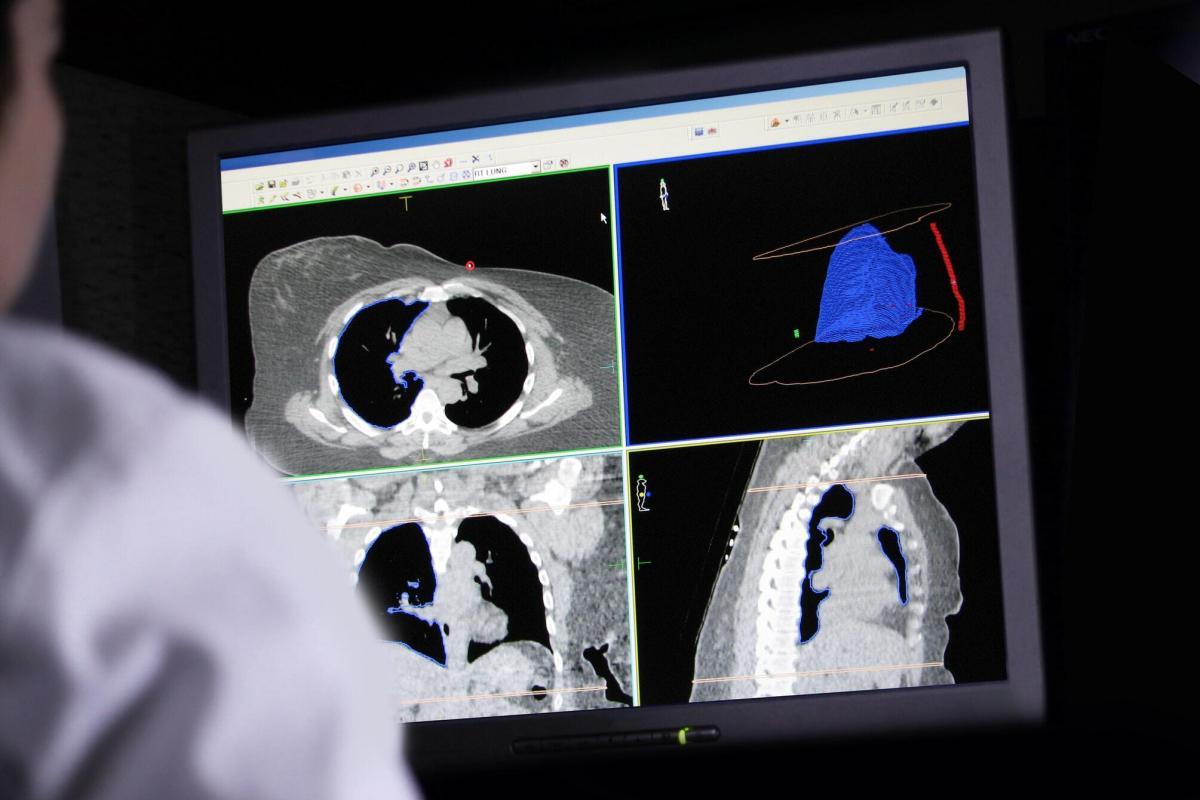

Radiation therapy is another cornerstone of cancer treatment, involving the use of high-energy particles or waves, such as X-rays or gamma rays, to destroy or damage cancer cells. Unlike chemotherapy, radiation therapy is typically localised, targeting specific areas of the body. It is often used in conjunction with surgery to shrink tumours before removal or to kill any remaining cancer cells post-surgery.

Advances in radiation therapy include techniques like intensity-modulated radiation therapy (IMRT) and stereotactic body radiation therapy (SBRT), which allow for more precise targeting of tumours, sparing surrounding healthy tissue. Proton therapy is another cutting-edge approach that uses protons instead of photons to deliver radiation, reducing damage to adjacent normal tissues.